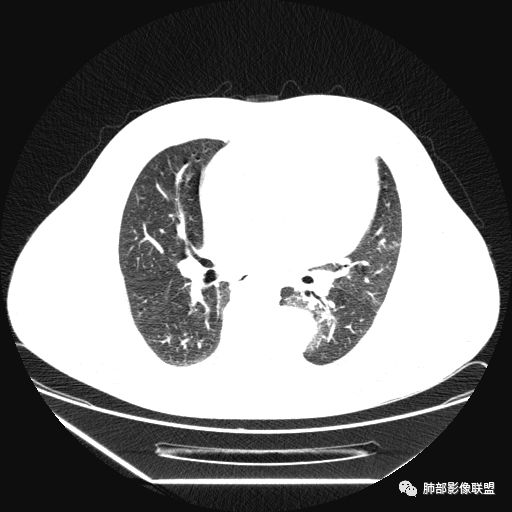

曹志勇:右肺尖后段类圆形病灶,边界清边,缘锐利,宽基底与胸膜相连,环形强化,内似见蛇纹血管征,考虑胸膜孤立性纤维瘤,右肺外底段病灶,考虑炎性可能大

红日东升:左侧胸椎旁肿块,边缘清晰光整,冠状位见D字征,未见支气管进入,肺组织受压表现,定位肺外。轻度强化,密度稍不均匀,临近肋骨变细,未见肺动脉供血,考虑良性肿瘤,神经源性可能。右肺下叶病灶,轻度强化,血管显影,边缘平直、凹陷,考虑炎性病变。

1.左上胸内脊柱旁半圆形肿块,质地坚实,密度比较均匀。

2.病灶周边见胸膜掀起,应当考虑胸壁或是纵隔来源,肺内病变不会如此。

综上,病灶定位胸壁或后纵隔,就发病率而言,神经源性可能性较大。